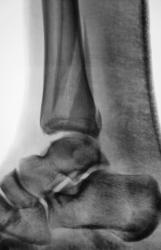

Пол пациента: Мужской пол Тип патологии: Травма Область исследования: Скелетно-мышечная система Методы исследования: Rg Пациенту в ургентном порядке был произведен "первичный снимок". Сегодня пациента доставили на "контрольный снимок". Какие мнения будут уважаемые коллеги? 1.REp_..jpg 2.REp_..jpg 3.REp_..jpg 4.REp_.jpg ВложениеРазмер 1.REp_..jpg70.64 КБ 2.REp_..jpg90.44 КБ 3.REp_..jpg84.75 КБ 4.REp_.jpg72.61 КБ Ср, 09/12/2009 - 20:21 #1 Иринка Не на сайте Был на сайте: 11 лет 5 месяцев назад Зарегистрирован: 16.11.2009 - 22:14 Публикации: 190 Трёхлодыжечный перелом с разрывом дистального межберцового синдесмоза и подвывихом стопы кнаружи. Репозиция неудовлетворительная, показано оперативное лечение. Ср, 09/12/2009 - 20:25 #2 v1tal Не на сайте Был на сайте: 4 года 9 месяцев назад Зарегистрирован: 07.06.2008 - 19:41 Публикации: 1779 На оперативное разрешение все "бонусы" собраны. "Знаешь, у некоторых врачей есть комплекс мессии — им необходимо спасать мир. А у тебя комплекс Рубика — тебе необходимо решать головоломки."

Трёхлодыжечный перелом с разрывом дистального межберцового синдесмоза и подвывихом стопы кнаружи. Репозиция неудовлетворительная, показано оперативное лечение.